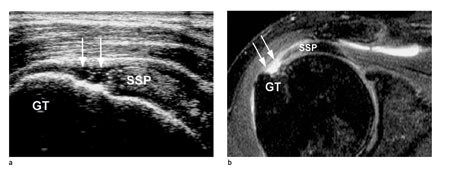

I de fleste tilfeller er ultralyd tilstrekkelig, målrettet MR rekvireres på utvidede indikasjoner ved atypiske funn og preoperativt. For pasienter med atraumatiske skulderlidelser vil klinisk undersøkelse eventuelt supplert med dynamisk bilateral ultralyd vanligvis gi tilstrekkelig grunnlag for konklusjon. For vurdering av rotatorcuffen inkludert rupturer samt bicepssenen er MR og ultralyd likeverdige (15), men pasientene er mer fornøyd med ultralyd (16). Ultralyd er beste metode for å vurdere kalknedslag. Figur 3 viser ultralyd og MR ved supraspinatusruptur. For revmatologen er ultralyd et nyttig hjelpemiddel for å skille mellom synovitt og tenosynovitt. Radiologiske forandringer ses hos de fleste pasienter med revmatoid artritt få år etter sykdomsdebut. Synovial inflammasjon kan medføre bruskforandringer og forringe skulderfunksjonen. Skjelettrøntgen med «outlet view» (fig 4) er først og fremst indisert ved traumatiske skulderlidelser, men kan gi opplysninger om større påleiringer på undersiden av akromion, grad av glenohumeral artrose og om sjeldne tilstander, slik som nekrose av caput humeri. Artrose i akromioklavikulærleddet ses hyppig hos pasienter eldre enn 50 år, men er vanligvis ikke smertefullt.